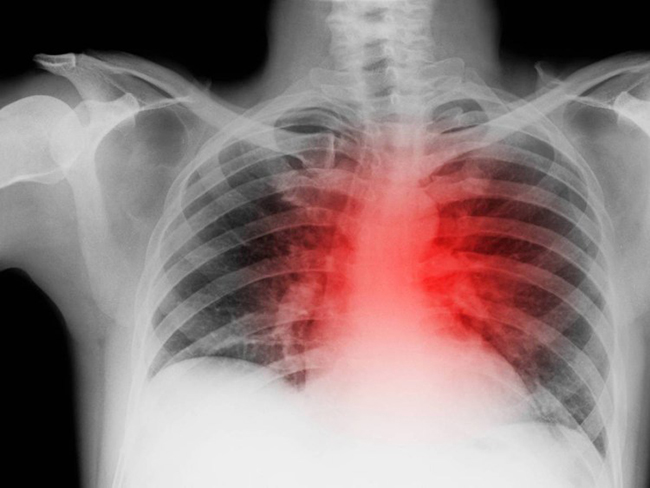

არტერიული წნევა ჩადგება ნორმაში, ეს კი იმას ნიშნავს, რომ ინსულტისა და გულ-სისხლძარღვთა დაავადებების გაჩენის რისკი საგრძნობლად შემცირდება.

2 კვირაში შეგიჩერდება ხველა. ის მაშინვე არ გაივლის, რადგან შენს ფილტვებს დრო სჭირდება აღსადგენად და დაგროვილი მავნე ნივთიერებების გამოსადევნად. ასევე მთლიანად აღგიდგება სისხლის მიმოქცევა, რაც გავლენას მოახდენს შენს სქესობრივ ცხოვრებაზე.

ბევრად იკლებს სხვადასხვა დაავადების გაჩენის რისკი. სიმსივნის წარმოქმნის შანსი იგივე გახდება, რაც არამწეველ ადამიანებში.